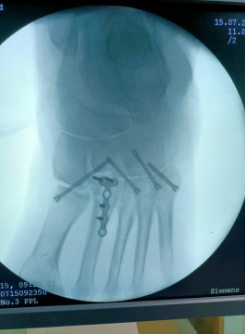

64岁的张大爷不小心摔倒跌伤后,发觉左脚脚踝处非常疼痛不能动弹,他连忙叫家人送来我院治疗。经诊断,张大爷左跗跖关节骨折脱位。

得知老人焦虑的状态后,骨伤科主任周建全及时与患者沟通交流,安抚好患者的情绪,并为患者制定了最佳诊疗方案——“骨折有限切开复位内固定手术”,整个治疗过程痛苦少、费用低、恢复快。

周建全说"骨折有限切开复位内固定手术”从外面来看,仅是一个非常小的切口,在足跟部这个敏感部位能做到小创伤,有着传统手术方法绝对无法比拟的优势,不仅能促进骨折完全复位,减少用药剂量,更能缩短住院时间,有效减轻患者的痛苦。